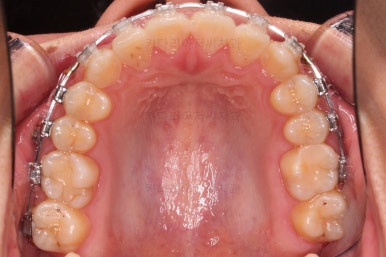

초기 6개월 이내에 어느 정도 치열이 가지런해 졌네요.

중간평가 들어갑니다.

앞니가 많이 뻗쳤나요?

그렇지 않죠.

대신 처음에는 삐뚤어서 가려져 있던 부정교합이 드러나면서 최소한 윗니는 교합을 위해 후방이동이 필요한 상황이긴 했습니다.

치열의 고른 느낌 좋고요.

덧니, 교합, 중앙선 등 모든게 좋아졌네요.